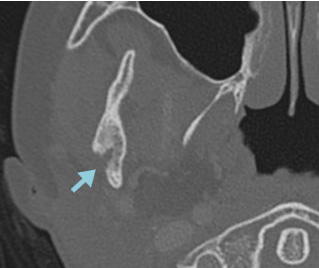

症例:7歳

右下顎骨にLCHの骨再発をきたした。HU内服治療を開始後、溶骨部分の順調な修復が認められた。

CT 骨条件

2か月後  4か月後

4か月後 * 患者さんから許可を得て掲載しています。